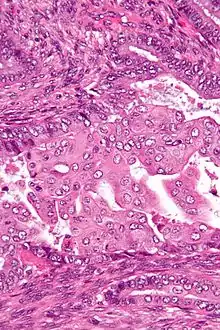

| Micrograph of an atypical polypoid adenomyoma. H&E stain. | |

APAs are characterized by glands with abnormal shapes that: (1) often have squamous metaplasia, and (2) are surrounded by benign smooth muscle.[1] Nuclear atypia, if present, is mild.

The microscopic differential diagnosis includes endometrial carcinoma and endocervical adenocarcinoma.